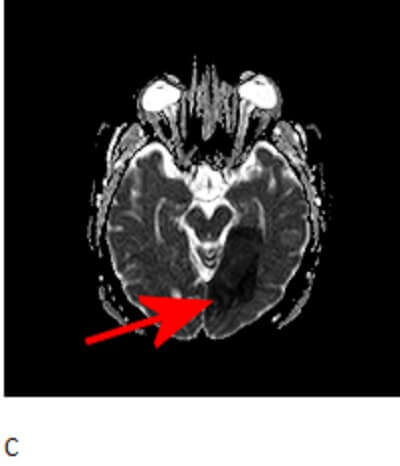

Diagnosis: Acute left posterior cerebral artery stroke.

Figure 1: Red arrows. A. Axial non-contrast head CT demonstrates hypoattenuation of the left medial occipital lobe with loss of grey white differentiation. B and C. Axial diffusion weighted (DWI) and apparent diffusion coefficient (ADC) images demonstrate respectively increased and decreased signal in the occipital cortex.

The paired posterior cerebral arteries supply portions fo the thalamus, lateral ventricle, midbrain occipital and inferomedial temporal lobes. Patients with acute PCA territory infarcts typically experience visual symptoms which can range from honomymous hemianopsia to cortical blindness depending on the extent of the stroke.